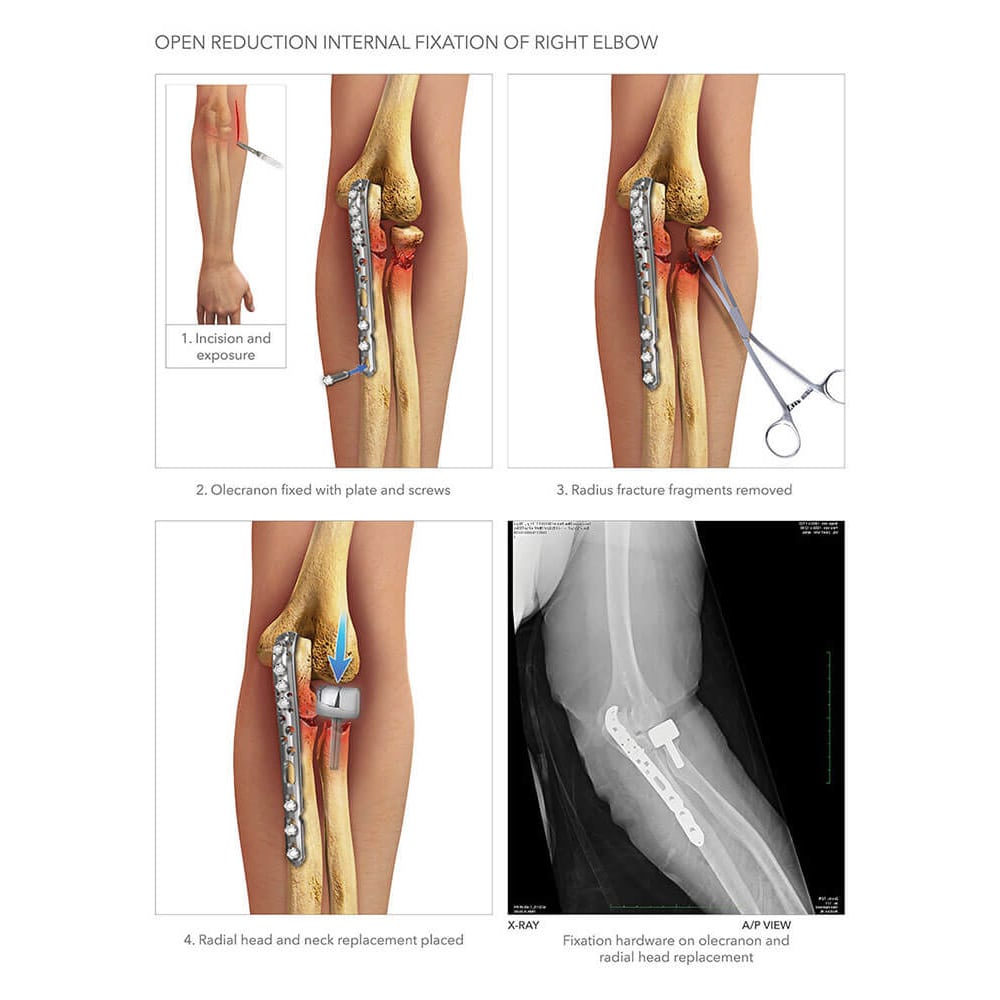

The Elbow Fracture ORIF Procedure: Step-by-Step

Understanding the ORIF procedure can help patients prepare mentally and physically for the surgery. Here’s a general overview of what to expect during an elbow fracture ORIF:

- Anesthesia administration: General anesthesia is typically used to ensure the patient is unconscious and pain-free during the procedure.

- Incision and exposure: The surgeon makes an incision over the fracture site to access the broken bones.

- Fracture reduction: Bone fragments are carefully realigned to their proper anatomical position.

- Internal fixation: The surgeon selects and applies appropriate fixation devices (e.g., plates, screws) to hold the bone fragments in place.

- Wound closure: The incision is closed using sutures or staples, and a sterile dressing is applied.

- Post-operative imaging: X-rays are taken to confirm proper alignment and fixation of the fracture.